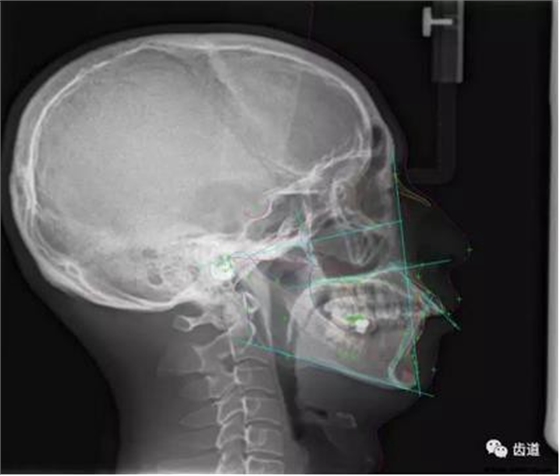

五)口腔正畸

CBCT在頜骨正畸科方面的應(yīng)用:軟件功能的強(qiáng)大,提供有效的數(shù)據(jù),為頜骨正畸提供了極大的幫助,免除了很多臨床醫(yī)生的手工繪圖,并有利于科研、教學(xué)等方面發(fā)展研究。

投影測量側(cè)位片影像

軟件產(chǎn)生CEPH圖像注釋,不含X線射線圖像